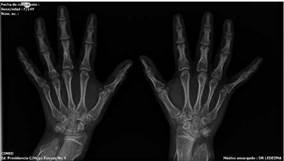

Fuente: Cortesía del Dr. Ledezma, CEMED.

Figura 1:

Proyección AP de ambas manos muestra lesiones líticas intramedulares (encondromas) radiolúcidas de márgenes definidos, con zona de transición estrecha, patrón de destrucción geográfico, que respetan la cortical sin reacción perióstica y levemente expansivas, la lesión más representativa está localizada en la tercera falange proximal de la mano izquierda, en su extremo proximal.